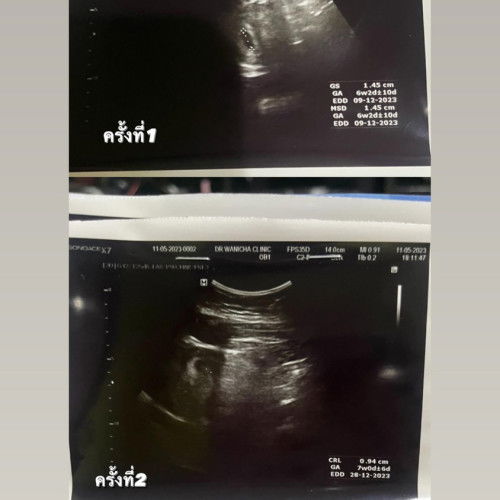

ครั้งแรกตอน 6 วีค ครั้งที่สอง 10วีค 4 วัน น้องได้มีการเจริญเติบโตไหมค่ะ แล้วเด็กประมาณนี้ตามเกณฑ์ต้องขนาดไหนค่ะ กังวลค่ะ น้องที่รู้จักท้อง10วีคซาวด์มา 3 เซนกว่า ต่างจากของเรามากๆค่ะ ปล.ซาวด์ครั้งที่2ในใบขึ้นแค่7 #คุณแม่ๆช่วยแนะนำหน่อยค่ะ #ท้องสองค่ะท้องแรกแท้ง